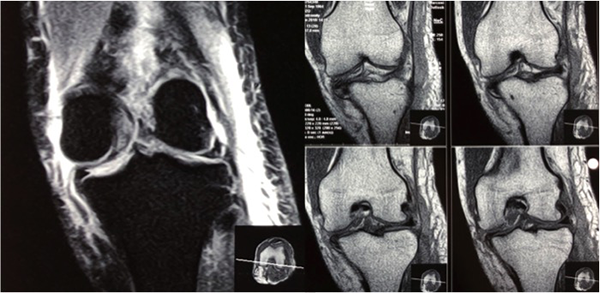

A los tres meses del accidente, una vez rehabilitadas las fracturas expuestas en mano y pie izquierdo, la rodilla presentó un examen físico compatible con secuela de lesión inestable de ligamento colateral interno con bostezo grado II (++/+++) con tope laxo en 30° de flexión y en extensión completa. No presentó derrame articular. Se observó desplazamiento posterior de tibia estructurado. Cajón posterior grado III (sin tope neto) y Godfrey positivo. Lachman positivo con pivot shift positivo. Rango de movilidad completo sin bloqueo. Dolor en compartimiento interno tercio posterior. El score de Lysholm Tegner preoperatorio de 10 y 1 respectivamente. El estudio por resonancia magnética (RM) confirmó el diagnóstico (figs. 1 y 2). El espesor medido del tendón cuadricipital a 30, 40 y 50 mm de inserción proximal en rótula por este estudio en cortes sagitales fue de 10.2 – 9.1 – 8.7 mm, respectivamente (fig. 3).

Figura 1: RM de rodilla izquierda. Secuencia T2 y T1 en cortes coronales. Se observa lesión completa del ligamento colateral interno con compromiso de componente menisco femoral (hoja profunda) al momento del trauma.

Figura 2: RM cortes sagitales secuencia T1. Se observa la traslación posterior de la tibia. Tendón rotuliano laxo como signo de inestabilidad posterior. Lesión grado III del cuerno posterior del menisco interno, trazo oblicuo asociado a luxación de la tibia. Lesión completa de ambos ligamentos cruzados (LCA – LCP). Menisco externo sin lesión objetiva.